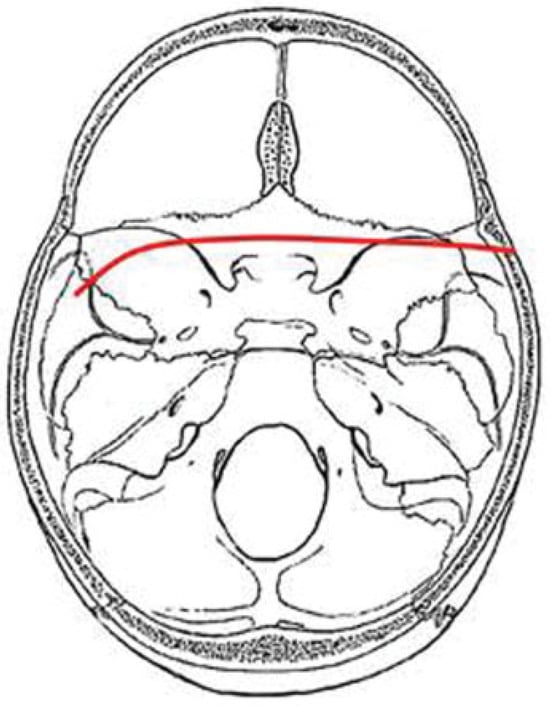

In our study we identified four major fracture patterns of transsphenoidal basilar skull fractures, which were: anterior transverse (AT), lateral frontal diagonal (LFD), posterior trans-verse (PT), and mastoid diagonal (MD), which matches Clark’s descriptions of the transsphenoidal basilar skull fractures.17

PT Pattern

PT fractures usually have a characteristic inverted U shape, with fractures extending from one temporal bone, across the middle cranial fossa to the posterior sphenoid body and clivus, then to opposite middle cranial fossa, and then on to the opposite temporal bone. The hallmark of this fracture pattern is the demonstration of a transverse fracture through the posterior sphenoid sinus or clivus. The exact location of this fracture occurs most frequently at the posterior wall of the sphenoid sinus but sometimes a few millimeters anterior or posterior to this location. The fracture usually results from lateral impact to the skull and enters the skull base in the tympanic portion of the temporal bone anterior to the external auditory canal and inferoposterior to the mandibular fossa of the temporal bone (Figure 7).

Figure 7. Composite drawing of the posterior transverse pattern (left impact).